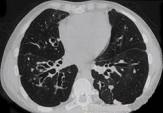

男,18岁,咳嗽,咳痰,咯血半月余,CT如图.选出最可能的诊断 ( )A.过敏性肺炎B.支气管扩张C.原发性肺结核D.大叶性肺炎E.肺癌

问题 男,18岁,咳嗽,咳痰,咯血半月余,CT如图.选出最可能的诊断 ( )

选项 A.过敏性肺炎 B.支气管扩张 C.原发性肺结核 D.大叶性肺炎 E.肺癌

答案 B